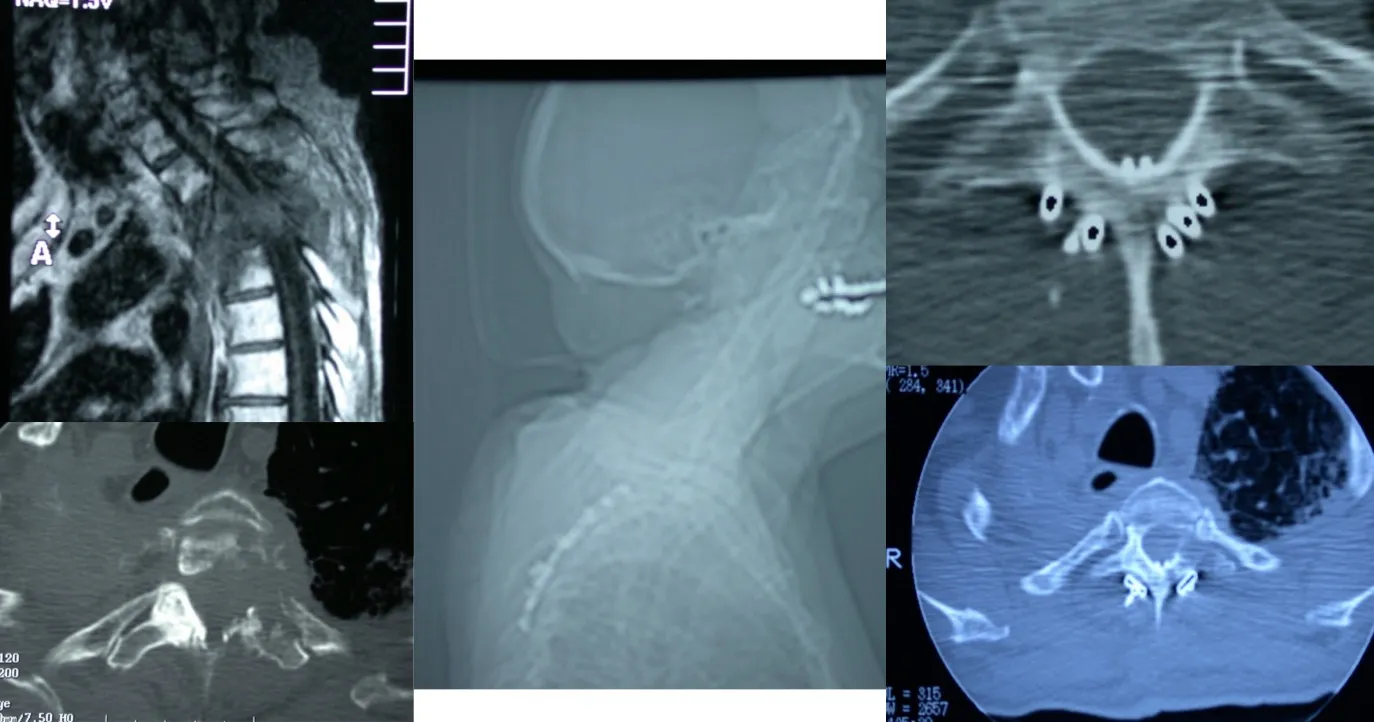

Estos son abordajes anterolaterales al tórax, que permiten abrir la cavidad torácica de forma más o menos invasiva según el caso, con el objetivo de acceder directamente a la columna torácica para extirpar o tratar tumores localizados en esa región. Este tipo de acceso ofrece una excelente exposición del campo quirúrgico y facilita la resección completa de las lesiones vertebrales anteriores.

También es posible realizar el abordaje por vía posterior, a través del cual se pueden efectuar tanto la resección de los tumores como la colocación de los sistemas de fijación necesarios para estabilizar la columna, tal como se observa en la figura. Este abordaje permite al cirujano acceder directamente a las estructuras posteriores vertebrales y realizar una descompresión neurológica precisa cuando existe afectación del canal raquídeo.

En el caso de la transición entre la columna torácica y la lumbar, la cirugía resulta especialmente compleja debido a la presencia del diafragma y a las particularidades anatómicas de esta región. En estas situaciones pueden ser necesarios abordajes combinados o específicos, que permitan acceder tanto por vía anterior como posterior. A menudo es preciso reconstruir el soporte anterior de la columna mediante injertos o prótesis para restaurar la estabilidad y garantizar que la columna se mantenga firme y alineada tras la intervención.